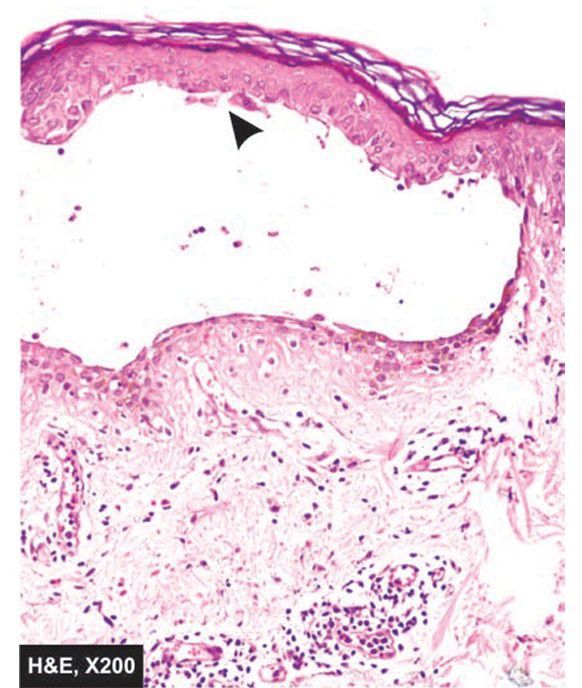

Pemphigus vulgaris.

An intraepidermal bulla in suprabasal location containing acantholytic cells (arrow) is seen.